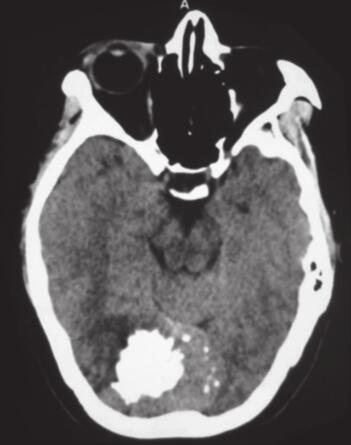

图1 术前头颅CT

CT示窦汇区稍高密度肿块,边界清楚,内见大片强化